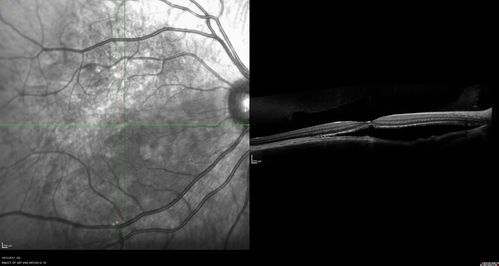

Choroidal Osteoma 13 Year Old

13 year old with 6 months of vision loss right eye and vision of 20/40